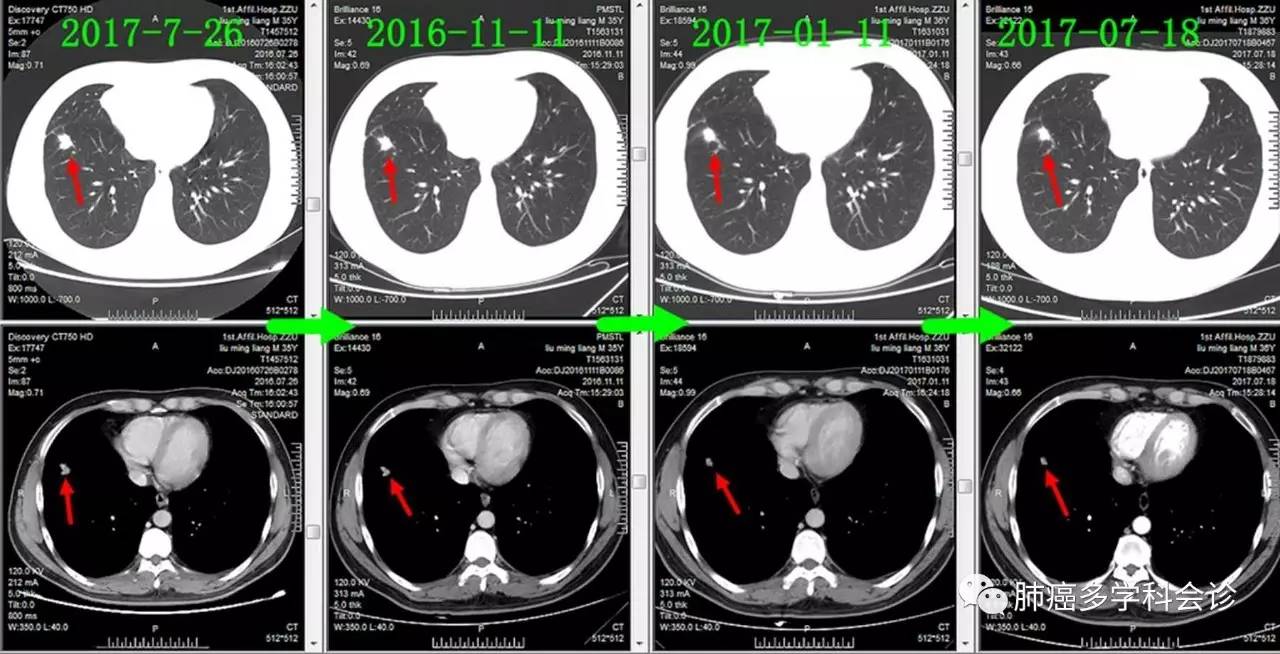

本周四下午,向与会的会诊专家们展示了一位年轻男性患者的 PET-CT 图像(2017-07-27),下图集中了患者体内的所有被发现的肿瘤病变。

下面通过对比治疗过程中胸部CT变化,展示胸部肿瘤此消彼长的过程:

• 肺原发灶略有缩小

• 纵隔肿大淋巴结逐渐缩小

• 胸膜转移灶消失

• 食管转移灶从小到大

下面着重展示食管转移灶的发展过程。从2016-09-13(完成2个周期化疗)开始,上下两图分别为各时间点CT的上下两层: